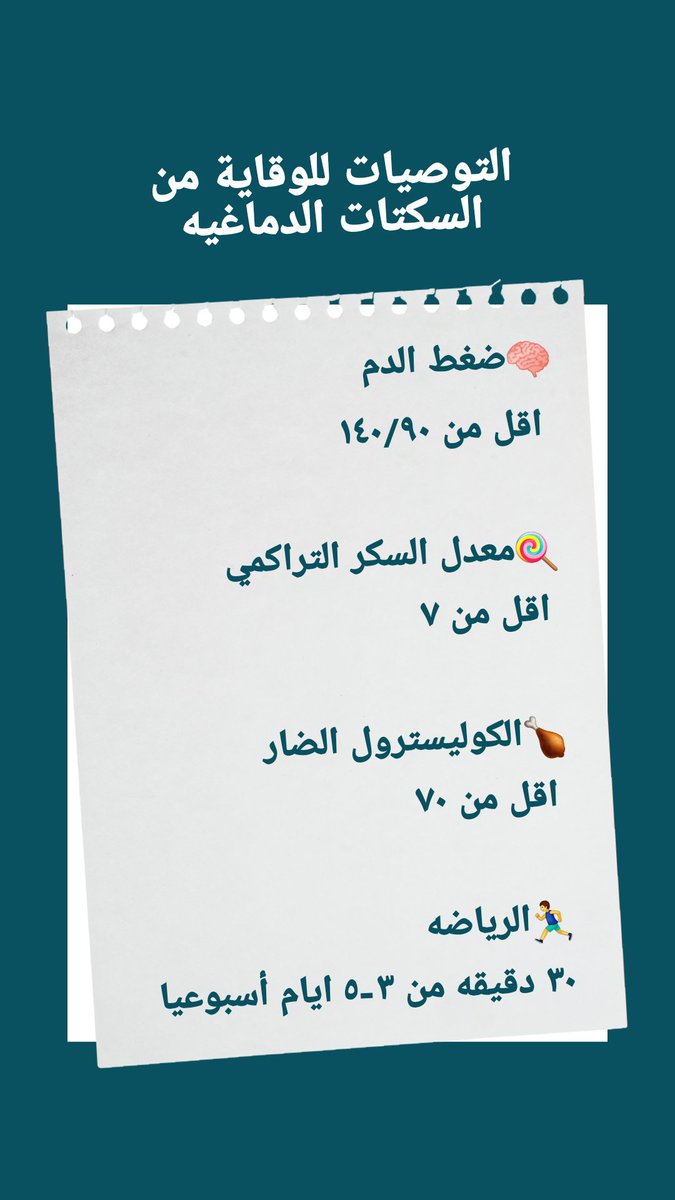

🧠العلاج الوقائي

خطوة هامه لمنع إعادة الاصابه مستقبلا

(معرفة السبب الأساسي والسيطرة عليه)

♦️متابعة

(سكر/ضغط/كوليسترول/تدخين/رياضه)

🧠العلاج الوقائي

خطوة هامه لمنع إعادة الاصابه مستقبلا

(معرفة السبب الأساسي والسيطرة عليه)

♦️متابعة

(سكر/ضغط/كوليسترول/تدخين/رياضه)